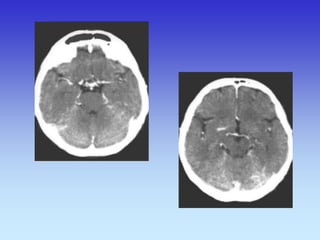

Grey Matter

White Matter

Occipital Lobe

Cerebellum

Frontal Lobe Lateral Sulcus

Parietal Lobe

Temporal Lobe

Gyri of cerebral cortex

Sulci of cerebral Cortex

Frontal Lobe

Temporal

Lobe

Occipital

Frontal Lobe Eye Ball

Parietal Lobe Occipital Lobe Transverse Sinus Cerebellar Hemisphere

Optic Nerve Maxillary Sinus